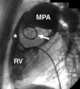

Prosthetic aortic valve replacement

Aortic valve replacement is a procedure whereby the failing aortic valve of a patient's heart is replaced with an artificial heart valve. The aortic valve may need to be replaced because: The valve is leaky (aortic insufficiency, also known as aortic regurgitation) The valve is narrowed and doesn't open fully (aortic stenosis)Current methods for aortic valve replacement include open-heart surgery, termed minimally invasive cardiac surgery (MICS) or surgical aortic valve replacement (SAVR) and transcatheter aortic valve replacement (TAVR). [Source: Wikipedia ]